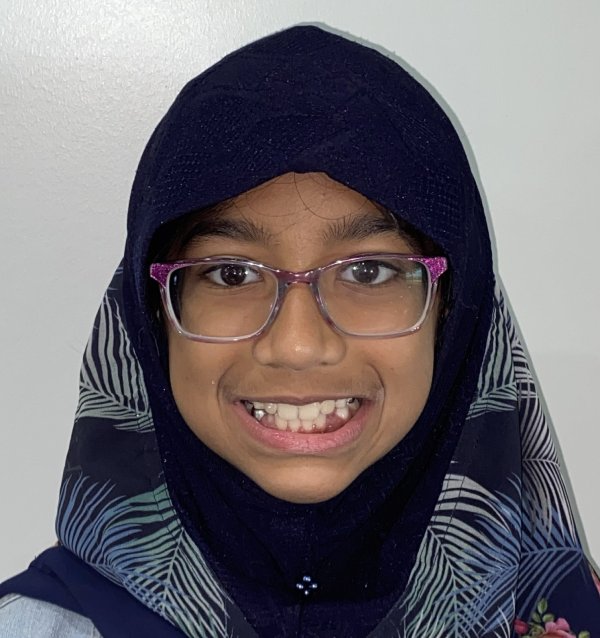

Actual Patient: Nusaybah

Before

Severe crowding, narrow jaws, blocked teeth

Front View

Top View

Right & Left Sides